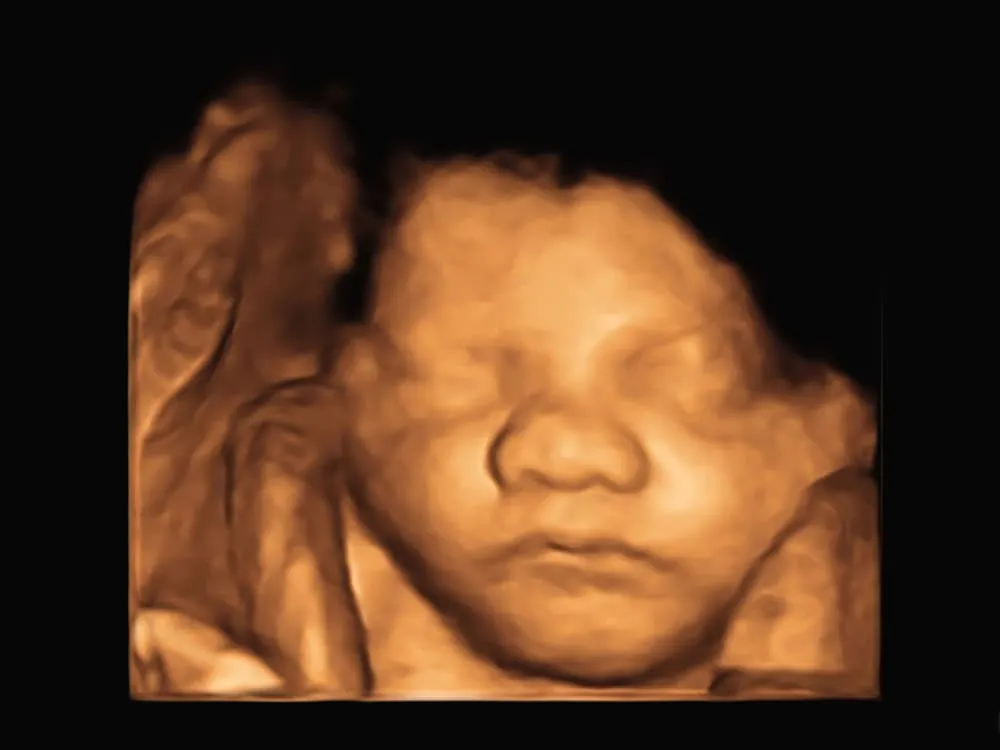

- Tóc bé mọc nhiều hơn: Nếu quan sát hình ảnh thai nhi 31 tuần trong bụng mẹ thông qua siêu âm, mẹ sẽ nhận thấy tóc bé mọc nhiều hơn. Mẹ có thể quan sát rõ khuôn mặt và các biểu cảm của bé.